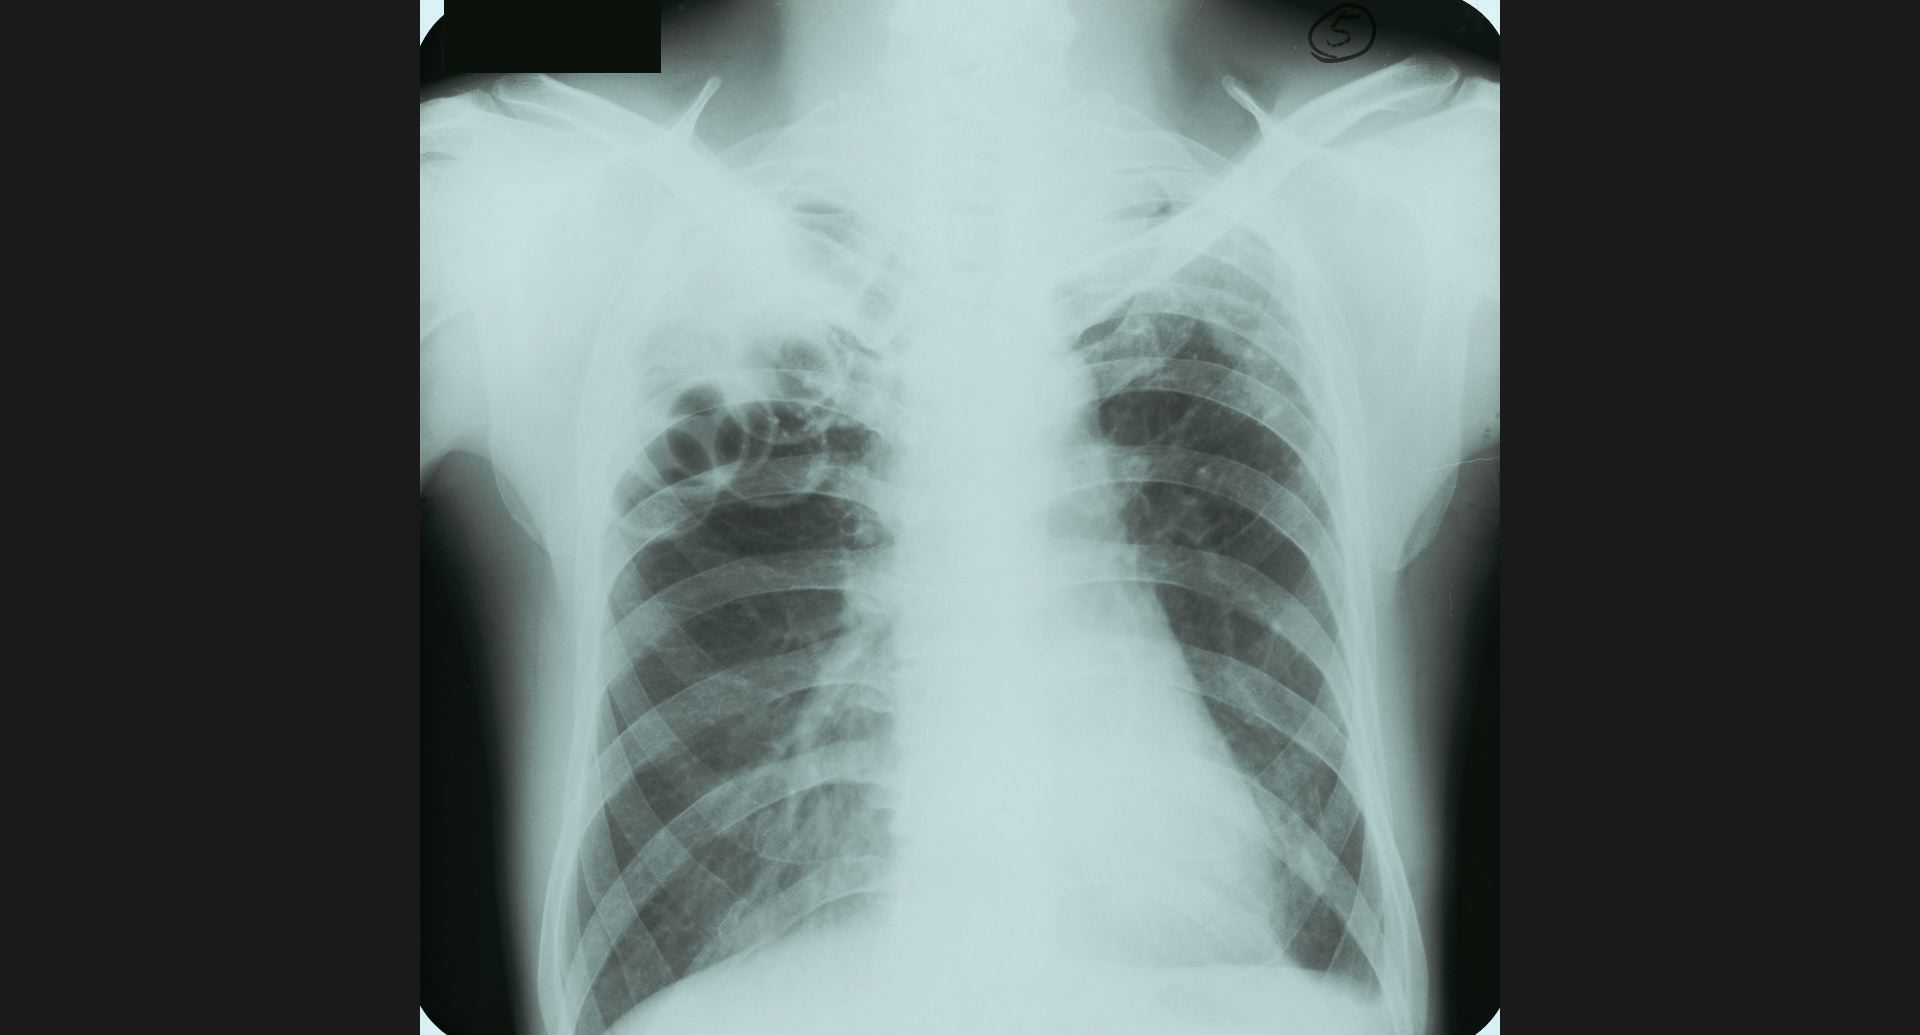

fig.1(117KB) :Alveolar microlithiasis

細かい肺病変、air bronchogram。